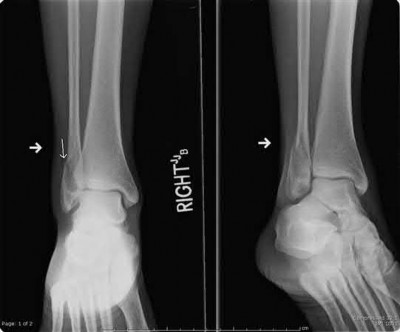

A 25-year-old male sustains an ankle fracture dislocation and undergoes open reduction and internal fixation. He returns to clinic five months following surgery complaining of continued ankle pain and instability with weight bearing. His immediate post-operative AP radiograph is seen in Figure A. Which of the following could have prevented this patient from developing persistent pain?

The patient presents with continued ankle pain and instability following open reduction and internal fixation. The radiograph in figure A demonstrates inadequate restoration of fibular length, likely leading to continued tibiotalar instability.

Illustration A demonstrates fibular malreduction with dislocation of the fibula anterior to the tibial incisura. Illustration B shows a comminuted fibula fracture along with a measurement of length from an intact fibula. The arc from the lateral process of the talus to the peroneal groove of the distal fibula is known as the "dime" sign and should remain unbroken if fibular length has been restored. Illustration C demonstrates the use of a push-pull screw and lamina spreader to regain length intraoperatively for a comminuted fibula fracture.

Chu and Weiner review management of malunions of the distal fibula. The authors state that restoration of fibular length, alignment and rotation leads to reduction of the talus, provides a buttress to talar motion in the setting of an incompetent deltoid, and allows the syndesmotic ligaments to heal at the appropriate tension.

Wikeroy et al conducted a study of patients from a prior prospective, randomized control trial comparing different methods of syndesmotic fixation. There was no significant difference in outcomes between tricortical or quadricortical 3.5mm screw fixation, however worse outcomes were seen with associated posterior malleolar fractures, obesity, a difference in sydesmotic width of 1.5mm or greater, and a CT confirmed tibio-fibular synostosis.

Sinha et al present a simple technique for fibular lengthening in the setting of distal fibula malunion. They found high union rates and improved AOFAS scores at short-term follow up with their technique.